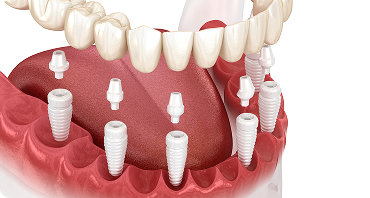

임플란트 틀니

치아가 전혀 없거나, 1-2개만 남기고 모두 없을 경우, 전체 임플란트를 통해

저작력과 심미성을 다시 살릴 수 있습니다.